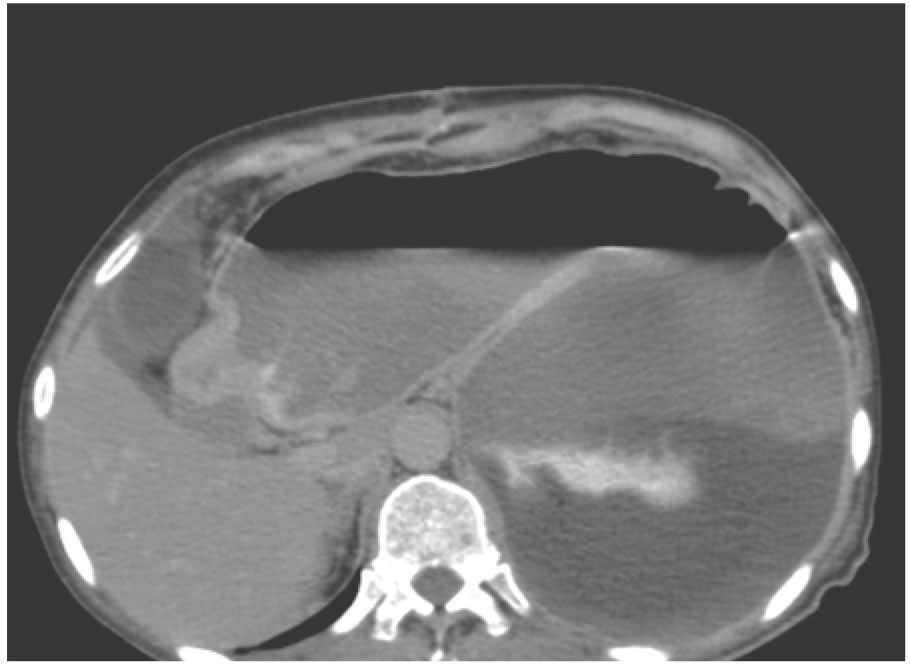

¿ Figura 2. TC que muestra divertículo gigante de sigmoides.

Hombre de 66 años con antecedente de diverticulosis colónica e historia de aproximadamente dos años de evolución con pérdida de peso, dolor abdominal inespecífico, cambio en los hábitos intestinales y palidez de tegumentos. Presentaba anemia microcítica hipocrómica, por lo que se realizaron estudios. El colon por enema informó enfermedad diverticular universal e imagen sugestiva de fístula colónico-gástrica por paso de medio de contraste (Figura 1). La colonoscopía demostró comunicación del colon con gran cavidad dilatada a 30 cm del margen anal. La tomografía evidenció un divertículo gigante de sigmoides (Figura 2). La laparotomía exploratoria permitió encontrar un divertículo gigante de sigmoides de 12 cm de diámetro (Figura 3). Se realizó sigmoidectomía y una colo-recto anastomosis, sin complicaciones (Figura 4).

El divertículo gigante de sigmoides es una rara complicación de la enfermedad diverticular del colon y recibe este nombre cuando es mayor de 4 cm de diámetro. Su fisiopatología es aún incierta, sin embargo, se acepta que el divertículo se forma por dilatación progresiva debido a un mecanismo de válvula unidireccional que impide la salida de aire a través de su comunicación con la luz intestinal. La resección segmentaria del colon afectado con el divertículo de manera electiva continúa siendo la opción más recomendada.